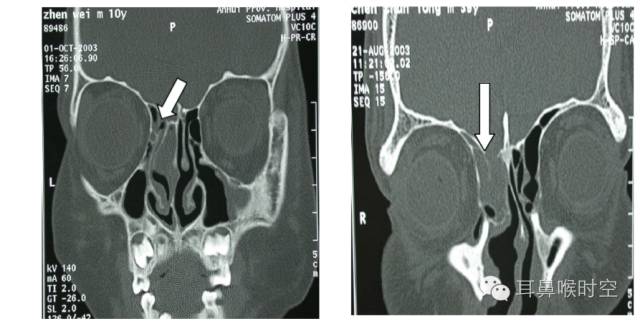

MRI显示额窦积液征与空泡蝶鞍

筛顶缺损和空泡蝶鞍

外伤性脑脊液漏